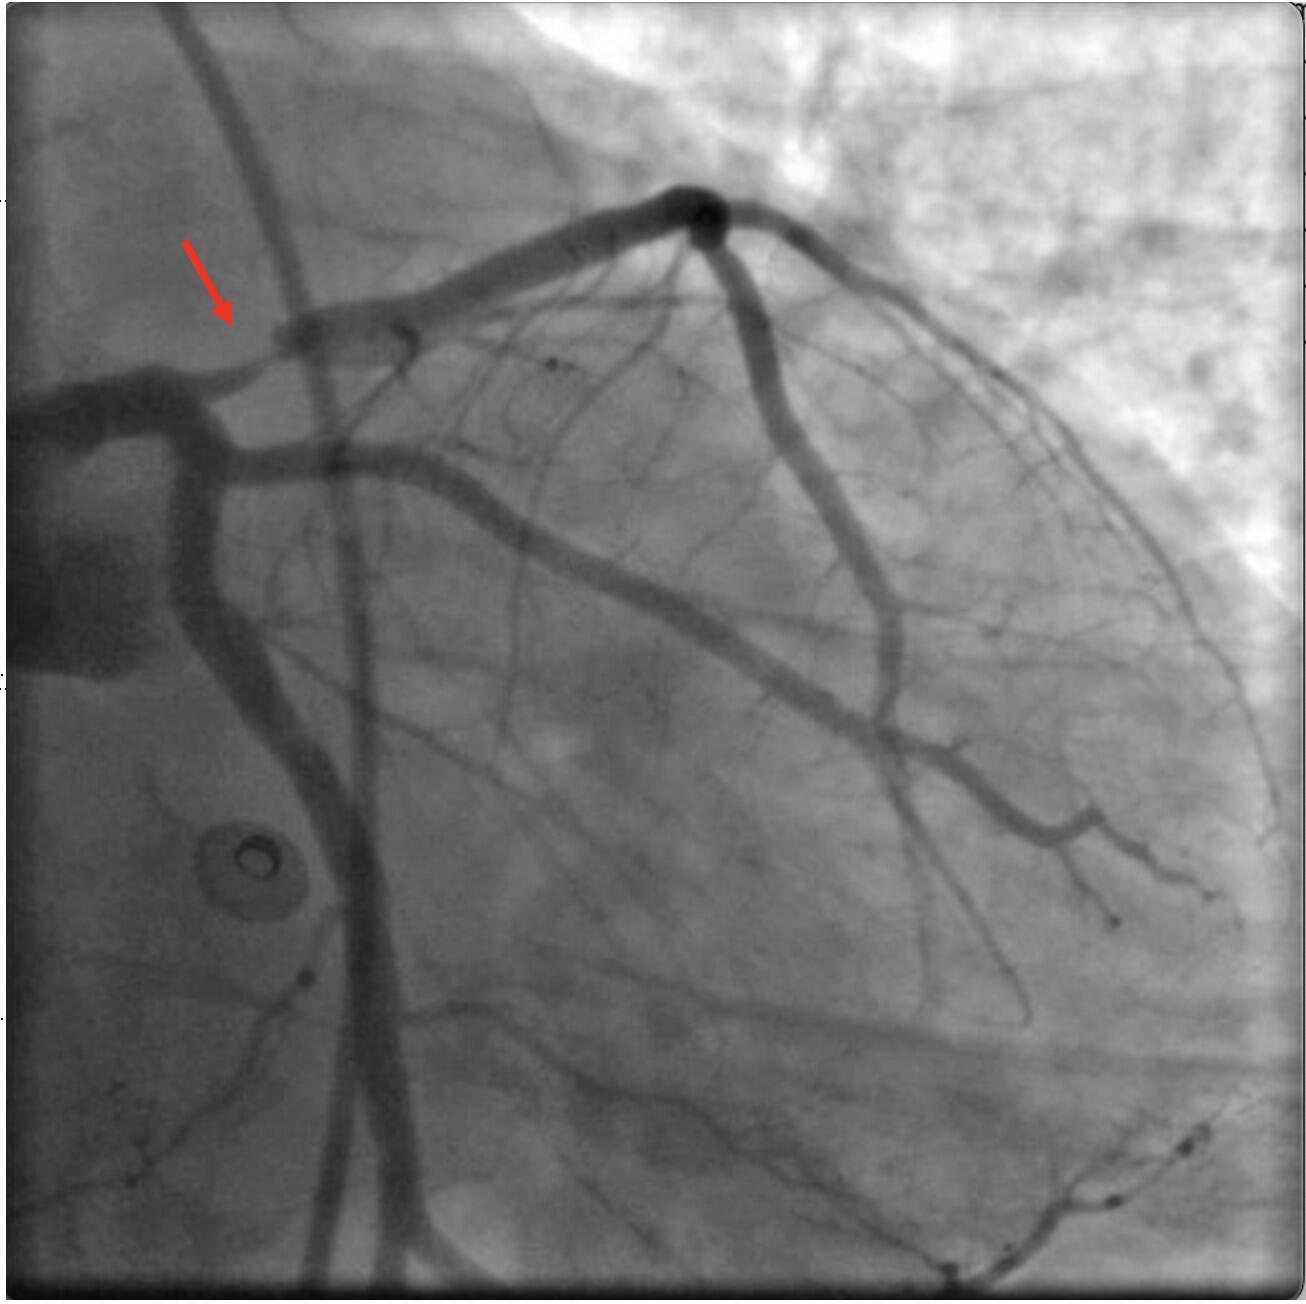

Susirgimo istorija surinkta iš partnerės: gyvenimo draugui retkarčiais pamausdavo širdies plote, tačiau į gydytojus nesikreipė, vaistų nevartojo. Rūkė, žinojo, kad padidintas cholesterolis, kraujo spaudimas, pirmos eilės giminaičiai sirgo širdies liga. Pavartodavo alkoholio. Dirbantis. Ligoninėje atliktuose tyrimuose nustatyta užsikimšusi kairioji širdies kraujagyslė, kuri atverta, implantuotas stentas. Ligonis išliko komoje. Neišgelbėtas“, – socialiniame tinkle rašė profesorius.

Susirgimo istoriją patikslino paciento žmona. Pasak jos, vyras jau kurį laiką skundėsi dusuliu fizinio krūvio metu, diagnozuota širdies liga. Prieš 10 metų atlikta chirurginė širdies operacija. Reguliariai vaistų nevartojo, pas gydytojus nesilankė. Ligoninėje atliktuose tyrimuose, rastas užsikimšęs širdies raumenį maitinantis šuntas, atlikta gydomoji procedūra. Tačiau vyras išliko gilioje komoje. Jo gyvybės išgelbėti nepavyko.

„61 metų vyras dėl įvykusios klinikinės mirties užsitęsusių lytinių santykių metu – nepavyko pasiekti tikslų – ir gaivinimo. Žmona patikslino, kad vyras, rodos, buvęs sveikas, vaistų nevartojęs. Kraujospūdžio nesimatavęs, cholesterolio nesityręs. Atliktuose tyrimuose reikšmingai padidintas cholesterolis, arterinės hipertenzijos sąlygota organų pažaida. Rasta okliuduota širdies raumenį maitinanti kraujagyslė. Gydymo eigoje pacientas išliko komoje, perkeltas palaikomajam gydymui į slaugos įstaigą“, – aprašė R. Kubilius.